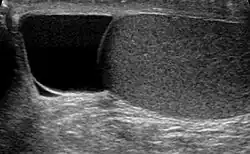

| Ultrasound of a testicle (grey) and a spermatocele (black). | |

The primary care physician may diagnose and manage benign causes of scrotal masses such as hydrocele, varicocele and spermatocele. However, if a "must not miss" diagnosis related to testicular masses such as testicular torsion, epididymitis, acute orchitis, strangulated hernia and testicular cancer is suspected, the family physician must refer to a urologist.[19] Finding a painless, cystic mass at the head of the epididymis that is clearly separate from the testicle can indicate a spermatocele. Shining a light through the mass, a process known as transillumination, can also help differentiate between a fluid-filled cyst and a tumor, which would not allow as much light to pass.[20] If uncertainty exists, ultrasonography of the scrotum can confirm the presence of a spermatocele.[7] The location and history of any scrotal masses are crucial in determining whether or not the mass is benign or malignant.[21] Lab tests such as a complete blood count (CBC test) or urine test can also be conducted to check for any possible infection or signs of inflammation.[22]